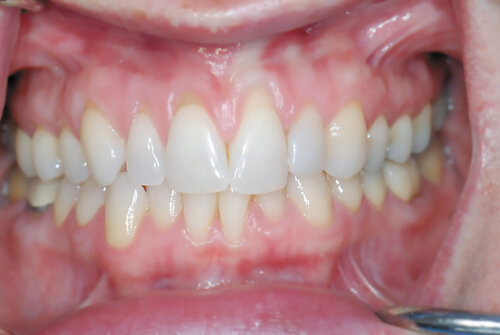

Before

The tooth length of the upper front teeth appears too short, making the teeth appear square shaped and showing too much gum tissue when the patient smiles.

After

We performed a simple gum lift procedure called crown lengthening to improve the shape of the teeth. The result makes them longer and more triangular, which is an aesthetic improvement.